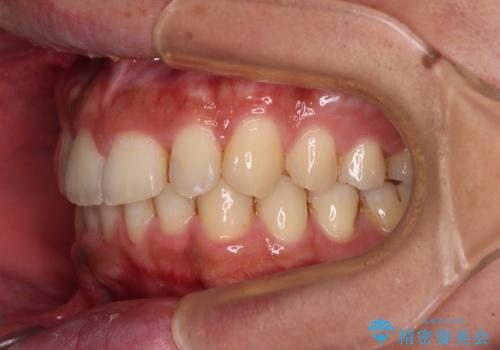

前歯のデコボコをスッキリ改善 インビザライン矯正

- 上下前歯のデコボコを気にして来院された患者様です。

全体的に叢生は軽度であったため、インビザラインにて矯正治療を行うこととしました。

デコボコの改善はもちろん、下顎前歯が隠れてしまうディープバイトも一緒に改善することができ、奥歯への負担を軽減することができました。